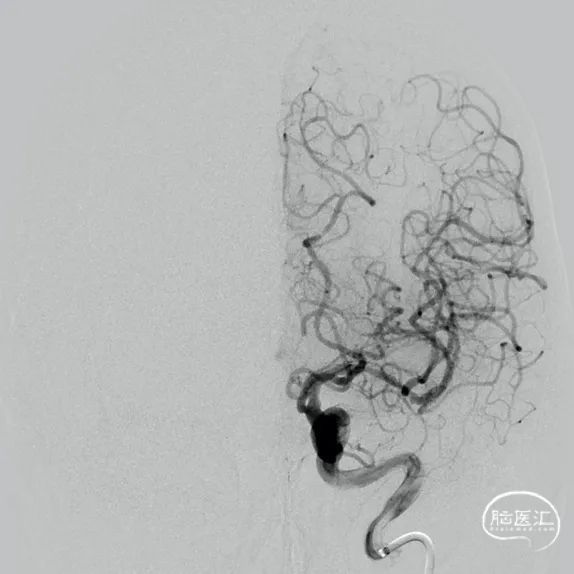

左侧颈内动脉造影显示左侧大脑中动脉M1段重度狭窄。

支架完全释放后造影显示支架打开良好、贴壁可。

术后造影显示左侧大脑中动脉血流较前改善,远端血管无缺失,残余狭窄约20%。